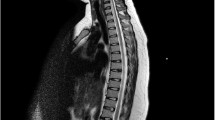

We report the case of a 1-month old, 28-week gestational age infant who presented with acute paraplegia after cardiopulmonary arrest. Later imaging confirms cerebral sinovenous thrombosis (CSVT) and a suspected infarction in the conus medullaris of the spinal cord. A prothrombotic state may explain the numerous areas of infarction visualized on neuroimaging. To our knowledge this is the first case report of acute and persistent paraplegia in an infant with CSVT and conus medullaris injury, which may be due to venous infarction of the spinal cord.